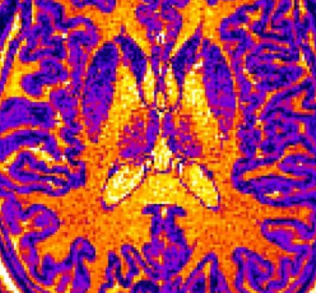

像这样的MRI图像通过机器学习计算机算法进行筛选。该算法基于大脑某些区域的厚度,体积或表面积的细微但统计上重要的差异,学会了识别非患者,诊断为自闭症的患者和诊断为精神分裂症的患者的大脑。该工具可能有助于使将来的心理健康诊断更加客观,而不是仅仅依靠患者及其家人的陈述。图片来源:CC-BY /东京大学小池真辅

医学和机器学习专家的多学科团队使用MRI(磁共振成像)脑部扫描对206名日本成年人,已经诊断出患有自闭症谱系障碍或精神分裂症的患者,被认为患有精神分裂症的高风险患者以及他们的第一例精神病患者,以及没有精神健康问题的神经型患者。所有患有自闭症的志愿者都是男性,但其他群体中的男性和女性志愿者数量大致相等。

机器学习使用统计信息来查找大量数据中的模式。这些程序在组内发现相似之处,在组之间发现差异,而这些差异经常发生,以至于不能被巧合地忽略掉。这项研究使用了六种不同的算法来区分患者组的不同MRI图像。

本研究中使用的算法学会了将不同的精神病学诊断与MRI图像中大脑的厚度,表面积或体积的变化相关联。尚不清楚为什么在特定的心理健康状况下经常发现大脑的任何物理差异。

训练期过后,又对另外43名患者进行了脑部扫描,对算法进行了测试。机器的诊断与精神科医生的评估相符,具有很高的可靠性和高达85%的准确度。

重要的是,机器学习算法可以区分非患者,自闭症谱系障碍患者和精神分裂症或精神分裂症危险因素患者。

研究小组还指出,大脑皮层的厚度,即大脑的顶部1.5至5厘米,是正确区分自闭症谱系障碍,精神分裂症和典型个体的最有用的功能。这揭示了皮质厚度在区分不同的精神疾病中所起的作用的重要方面,并可能指导将来的研究以了解精神疾病的原因。